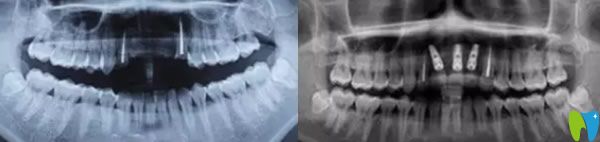

郝醫(yī)生通過醫(yī)學(xué)種植技術(shù),根據(jù)老公牙齒狀況設(shè)計(jì)種植方案。他將種植體與人體兼容性高的鈦金屬精準(zhǔn)植入缺牙區(qū)的牙槽骨內(nèi),等三個(gè)月后,人工牙和牙槽骨緊密結(jié)合,再做烤瓷牙、全瓷牙冠。郝醫(yī)生植入牙根手術(shù)完成后,老公從手術(shù)室出來牙齦看著就沒有之前那么憋了,飽滿了許多。

三個(gè)月后,我們又來到成都瑞爾口腔,醫(yī)生說恢復(fù)的很不錯(cuò),牙槽骨和種植體已經(jīng)緊密結(jié)合,可以安裝基臺,戴上牙冠后,牙齒咀嚼功能恢復(fù)了,可承受正常的咀嚼力量,美觀上幾乎和自然牙一樣。郝亦工醫(yī)生建議后期一定要保持好口腔衛(wèi)生健康,細(xì)心呵護(hù),這樣能夠保證種植牙的使用壽命。